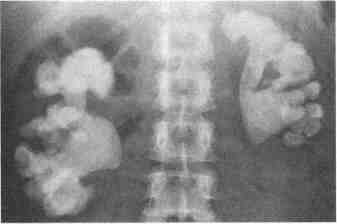

1. Как коралловидные камни получили свое название? Посмотрите на обзорную урограмму пациента с двухсторонними коралловидными камнями (рис. 76-1.). Теперь вы знаете. 2. Что является причиной их формирования? Большинство коралловидных камней обусловлены инфекцией и состоят из аммония и фосфата магния (струвита), а также фосфата кальция. Эти минералы преципи-тируют на матриксную "форму" чашечно-лоханочной системы, имеющую коралловидную конфигурацию. Ведущим патологическим звеном у таких пациентов является хроническое ощелачивание мочи, которое развивается в результате действия уреазообразующих микроорганизмов в моче. 3. Связано ли образование коралловидных конкрементов с инфекцией? Образование большинства коралловидных камней обусловлено инфекцией. Однако камни мочевой кислоты и цистиновые камни также могут иметь коралловидную конфигурацию. Наиболее часто встречающиеся камни, состоящие из оксалата кальция и фосфата кальция, редко достигают таких размеров и обычно не имеют коралловидной формы. 4. Следует ли удалять коралловидные камни, если они бессимптомны? Во многих исследованиях выявлено, что патогенез таких камней приводит к прогрес-сированию обструкции, присоединению инфекции и потере функции почек. Рис. 76-1. Двухсторонние коралловидные камни у женщины с рецидивирующей протейной инфекцией мочевыводящих путей Таким образом, наличие такого камня само по себе является показанием к вмешательству, даже если при этом нет симптомов 5. Как удалять коралловидные камни? В прошлом часто применялась "разъединяющая